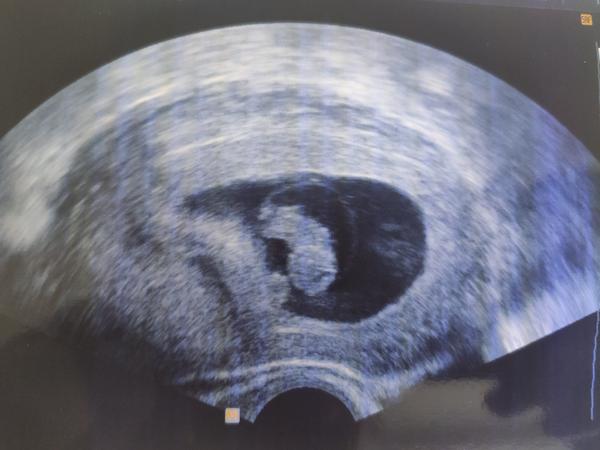

@vero987nika no ono v tomhle týdnu to stále zatím víc připomíná černobílou šmouhu než dítě 😅🙈

Fazole